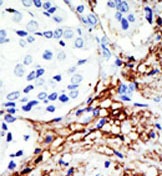

Supportive validation

- Submitted by

- Acris Antibodies GmbH (provider)

- Main image

- Experimental details

- Formalin-fixed and paraffin-embedded human breast carcinoma reacted with the primary antibody, which was peroxidase-conjugated to the secondary antibody, followed by DAB staining. This data demonstrates the use of this antibody for immunohistochemistry; clinical relevance has not been evaluated.